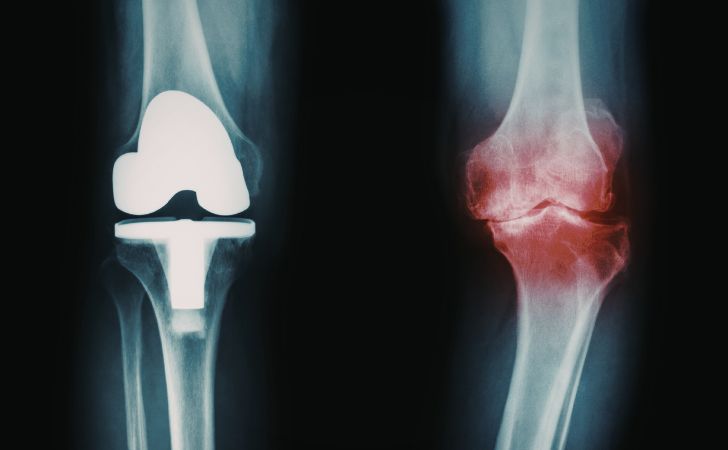

もう1つ、著しい変形性膝関節症(へんけいせいひざかんせつしょう)の患者様を担当した時の体験談を小話をとして書き留めておきます。

私が担当した患者様は外見上ものすごいO脚になっており、体を横に揺らすようにして歩いていました。膝に痛みもあり、また関節変形があるためにバランスを取るのが難しく、このような歩き方になっていると考えられました。

この方は人工膝関節置換術を受けることになり、術後のリハビリが始まりました。

上の画像の通り、人工の膝関節になると曲がっていた関節が真っ直ぐになります。

しかし、患者様は膝がまっすぐになったにも関わらず、体を横に揺らすようにして歩くのは変わらなかったのです。

一般に関節の変形は長い時間(数年から数十年)をかけて進行し、身体はその都度、身体の状態に合わせるように動きを選択します。

文字通り長年かけて適応してきた動きが、ものの数時間で膝がまっすぐになったからといって、すぐさま新しい膝と身体に適応して歩き方まで変わることはないでしょう。

つまり、このことからも手術や各種治療で関節の状態が変化したら、それに適応した身体の使い方を練習することが重要なのであり、病院で行われるリハビリテーションの大切さを改めて実感したケースでした。

本セクションのテーマの「痛みと回避行動」の1つの事例として書き留めておきました。